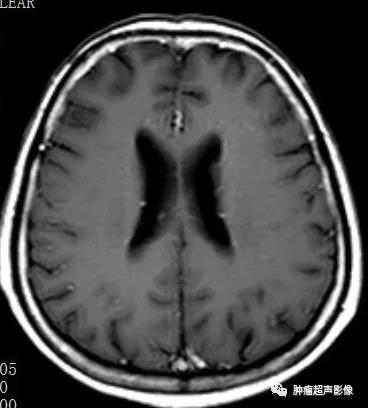

MR表现为两侧额枕叶皮层及皮层下多发结节或皮层增厚、脑回肥厚,FLAIR信号增高。

头颅CT示两侧侧脑室下多发小结节状钙化,增强MR示室管膜下结节明显强化。